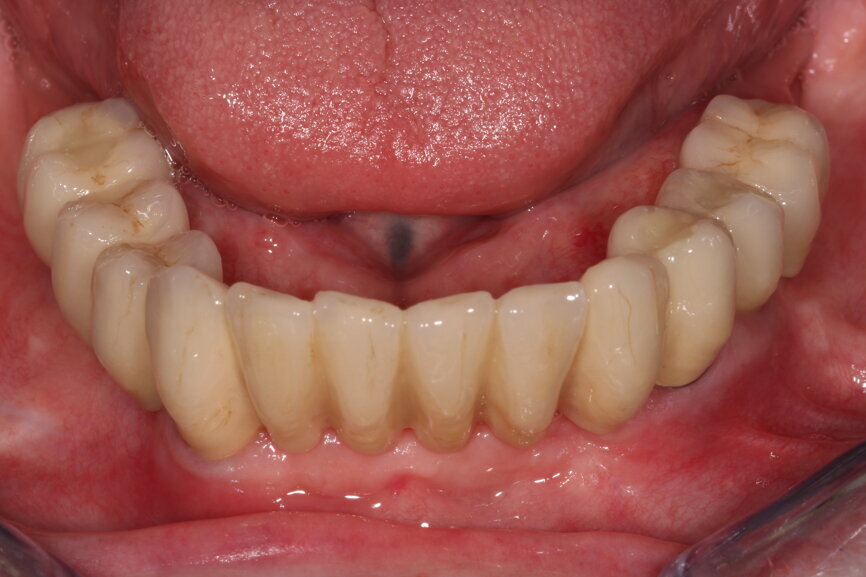

Fig. 13: Implant crowns in situ.

Once the implants are placed in situ and fully integrated, we then have a choice of conventional wet impression techniques versus digital intra-oral scanning. For the majority of cases, intra-oral scanning is extremely predictable and reliable—more so than conventional techniques—with milled (and lately printed) models having excellent properties and less accumulation of processing errors. However, deeply placed implants relative to adjacent teeth with deep contact points are very difficult to scan and pick up. Straumann tissue level implants offer a very straightforward restorative platform to scan from.

With greater numbers of implants and fewer teeth to act as reference points, intra-oral scanning becomes less reliable—particularly across the arch—so we need to exercise caution and be aware of its limitations. We have used composite flow stuck to the soft tissue to increase reference points for our scanners, increasing their ability to stitch images more accurately together. With this in mind, we cannot assume the scan is accurate and any framework fabricated would be non-passive; therefore, we must use other methods to verify the scan’s accuracy. We have found locking temporary abutments within a composite framework intra-orally the easiest and most reproducible way to do this. It then allows us to design and mill a truly passive framework by Createch and a temporary acrylic bridge.